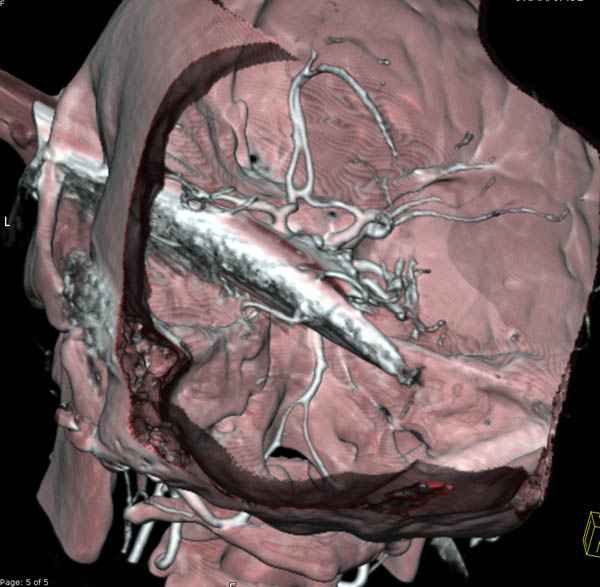

По протоколу сделаны все необходимые исследования: рентген, ангиограмма с 3Д реконструкцией, где обнаружили что все жизненно важные сосуды не задеты, даже некоторые "сидят" изгибаясь на ноже.